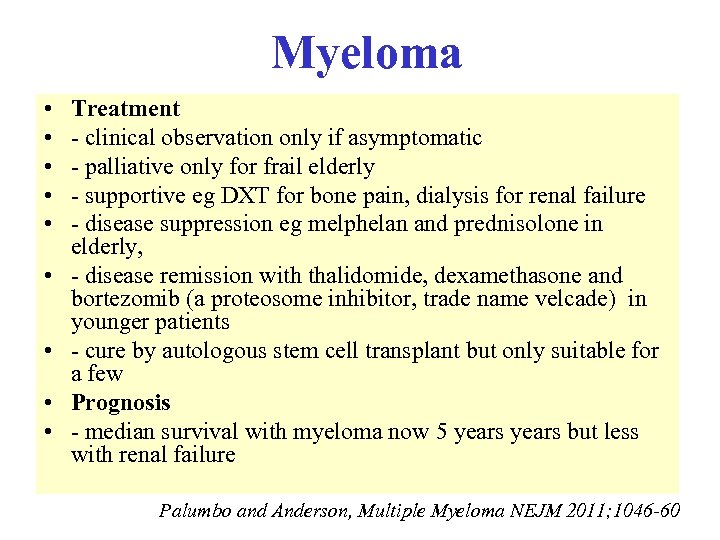

Myeloma • • • Treatment - clinical observation only if asymptomatic - palliative only for frail elderly - supportive eg DXT for bone pain, dialysis for renal failure - disease suppression eg melphelan and prednisolone in elderly, - disease remission with thalidomide, dexamethasone and bortezomib (a proteosome inhibitor, trade name velcade) in younger patients - cure by autologous stem cell transplant but only suitable for a few Prognosis - median survival with myeloma now 5 years but less with renal failure Palumbo and Anderson, Multiple Myeloma NEJM 2011; 1046 -60

Myeloma • • • Treatment - clinical observation only if asymptomatic - palliative only for frail elderly - supportive eg DXT for bone pain, dialysis for renal failure - disease suppression eg melphelan and prednisolone in elderly, - disease remission with thalidomide, dexamethasone and bortezomib (a proteosome inhibitor, trade name velcade) in younger patients - cure by autologous stem cell transplant but only suitable for a few Prognosis - median survival with myeloma now 5 years but less with renal failure Palumbo and Anderson, Multiple Myeloma NEJM 2011; 1046 -60